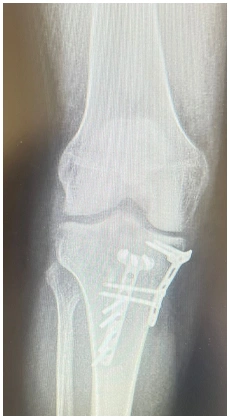

As osteotomias são procedimentos cirúrgicos que envolvem o corte e reposicionamento dos ossos ao redor da articulação do joelho para corrigir deformidades angulares, como a osteoartrose em estágio inicial ou instabilidade ligamentar. Esse procedimento visa redistribuir as forças na articulação do joelho e aliviar a pressão sobre as áreas danificadas da cartilagem.